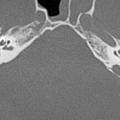

Temporal kemik fraktürleriTemporal kemik fraktürleri, genellikle künt kafa travması sonrası gelişir; %30-75. %71’i 11-40 yaş arasında görülmektedir. %76’sı erkektir. Genellikle, künt travma sonrası, kafaya yandan gelen travmalar sonucu meydana gelir. Temporal kemik fraktürlerin nedenleri ve tedavisi

Temporal kemik fraktürleriTemporal kemik fraktürleri, genellikle künt kafa travması sonrası gelişir; %30-75. %71’i 11-40 yaş arasında görülmektedir. %76’sı erkektir. Genellikle, künt travma sonrası, kafaya yandan gelen travmalar sonucu meydana gelir. Temporal kemik fraktürlerin nedenleri ve tedavisi